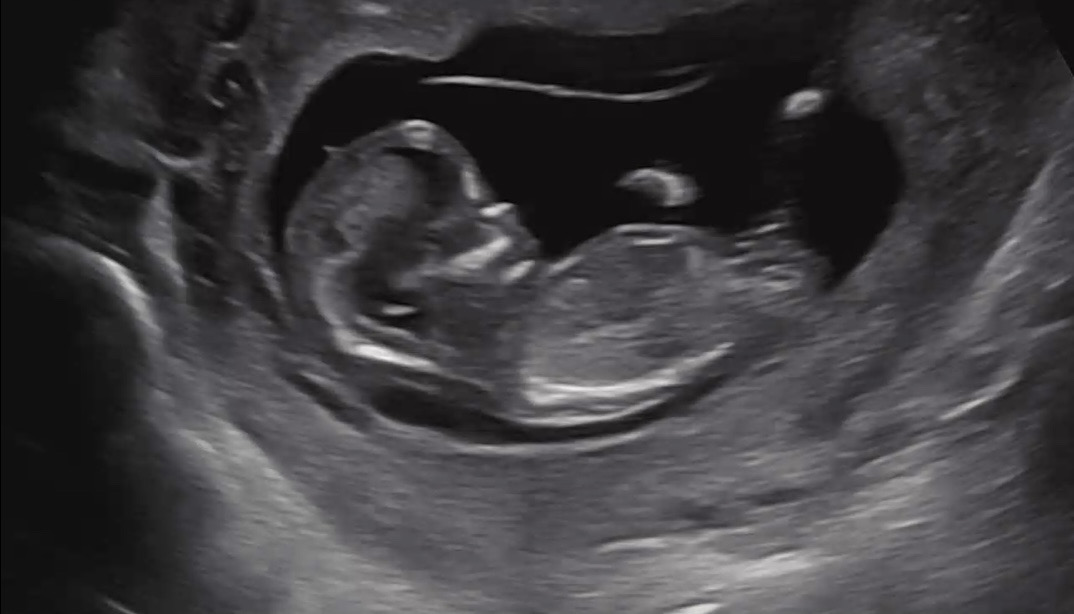

12주차 초음파 인데 각도법 고수님들 성별 예측부탁드려요 ~

12주차 초음파 사진입니다~ 성별이 너무너무 궁금해요 ㅠㅠ 각도법 고수님들 부탁드립니다~ 🥹🙏🏻